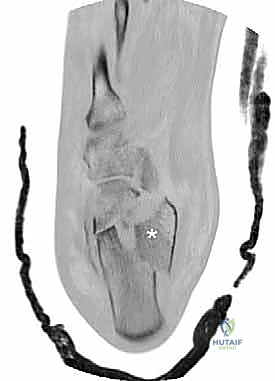

- التصوير بالأشعة السينية (X-rays): لأخذ فكرة أولية عن الكسر (زوايا بوهلر وجيسان - Bohler’s and Gissane’s angles).

- الأشعة المقطعية (CT Scan): وهي الخطوة الأهم والأكثر حيوية. توفر الأشعة المقطعية صوراً ثلاثية الأبعاد وتقاطعاً دقيقاً للكسر، مما يسمح بتصنيف الكسر (نظام ساندرز - Sanders Classification) وتحديد عدد الشظايا العظمية ومدى انزياحها داخل المفصل. بناءً على هذه الأشعة، يضع الدكتور هطيف خطته الجراحية الدقيقة.